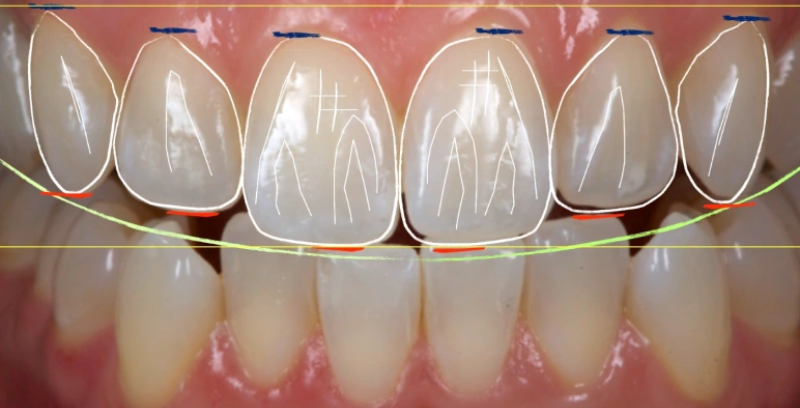

O serviço de Estética do Sorriso é ideal para quem busca realçar a beleza do sorriso de forma personalizada e harmônica. No Instituto Dr. Luiz Paulo Borges, oferecemos procedimentos modernos como clareamento dental, lentes de contato dentais e restaurações estéticas para devolver confiança e equilíbrio ao seu sorriso.

Veja o resultado do tratamento realizado pelos meus clientes

Cada transformação realizada é a prova do cuidado e da excelência que dedicamos aos nossos clientes. Nosso compromisso é elevar sua confiança, autoestima e bem-estar. Descubra como pequenas mudanças podem fazer uma grande diferença e inspire-se com histórias reais de quem já confiou em nosso trabalho.

O processo começa com uma avaliação detalhada para entender suas necessidades e desejos. Usamos imagens e modelos para planejar o tratamento e garantir que o resultado final atenda às suas expectativas.

Os procedimentos são realizados com técnicas avançadas, sempre priorizando conforto e segurança. Após o tratamento, você receberá orientações personalizadas para manter os resultados por mais tempo.